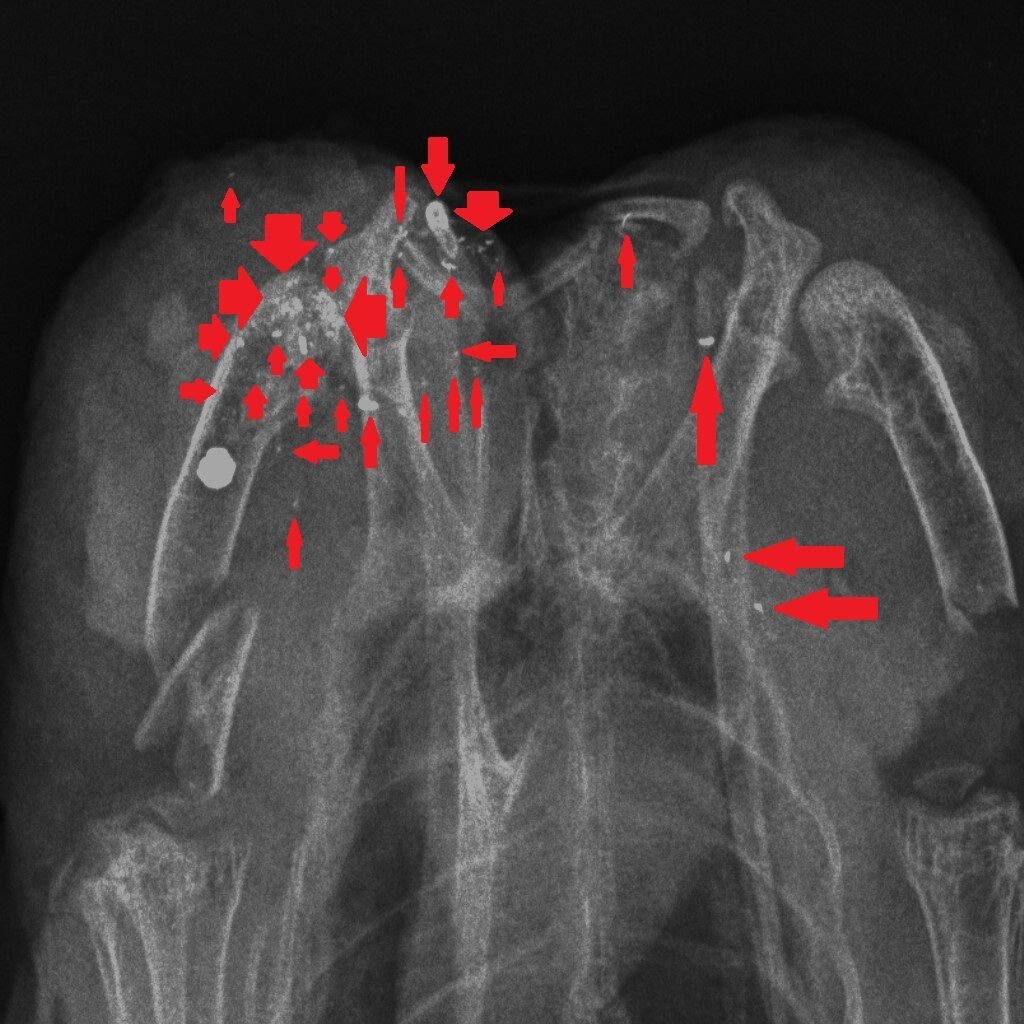

How could we reduce the risk of exposure to lead in game meat? It’s simple – stop shooting lead ammunition into animals that are destined for the human food chain. One of the useful properties of lead is that it is soft and malleable – that’s why, in the past, we have used it widely. But those same physical properties mean that lead passing through the flesh of a shot animal, hitting organs, soft tissue, bones and cartilage, shatters and tiny fragments of lead spread through the body of the animal. Here are three x-rays of shot birds that were bought in butcher’s shops and then x-rayed. The top x-ray is of a partridge and the other two are Red Grouse. Large white circular objects are lead shot. The green arrows point to fragments of bone and the red arrows indicate fragments of lead, from the shot, that have spread through the flesh.

Almost all of the fragments of lead are tiny – far too small to be detected in the cooking or eating process. Yes, you can spit out the almost-intact lead shot but you can’t get rid of the fragments. The lead analyses that have been done in studies cited above, and in our own, remove the lead shot and analyse the lead content of the meat after that removal. So when Sainsbury’s say that their game meat has no lead shot in it that’s good (although careful eating would remove those anyway) but they are not removing the tiny fragments of lead. So removing the almost intact lead shot particles is pretty irrelevant to the lead levels in the meat, as we will show you later this week…